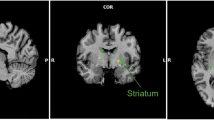

Consumption of high fat, high sugar (western) diets is a major contributor to the current high levels of obesity. Here, we used a multidisciplinary approach to gain insight into the molecular mechanisms underlying susceptibility to diet-induced obesity (DIO). Using positron emission tomography (PET), we identified the dorsal striatum as the brain area most altered in DIO-susceptible rats and molecular studies within this region highlighted regulator of G-protein signaling 4 (Rgs4) within laser-capture micro-dissected striatonigral (SN) and striatopallidal (SP) medium spiny neurons (MSNs) as playing a key role. Rgs4 is a GTPase accelerating enzyme implicated in plasticity mechanisms of SP MSNs, which are known to regulate feeding and disturbances of which are associated with obesity. Compared to DIO-resistant rats, DIO-susceptible rats exhibited increased striatal Rgs4 with mRNA expression levels enriched in SP MSNs. siRNA-mediated knockdown of striatal Rgs4 in DIO-susceptible rats decreased food intake to levels comparable to DIO-resistant animals. Finally, we demonstrated that the human Rgs4 gene locus is associated with increased body weight and obesity susceptibility phenotypes, and that overweight humans exhibit increased striatal Rgs4 protein. Our findings highlight a novel role for involvement of Rgs4 in SP MSNs in feeding and DIO-susceptibility.